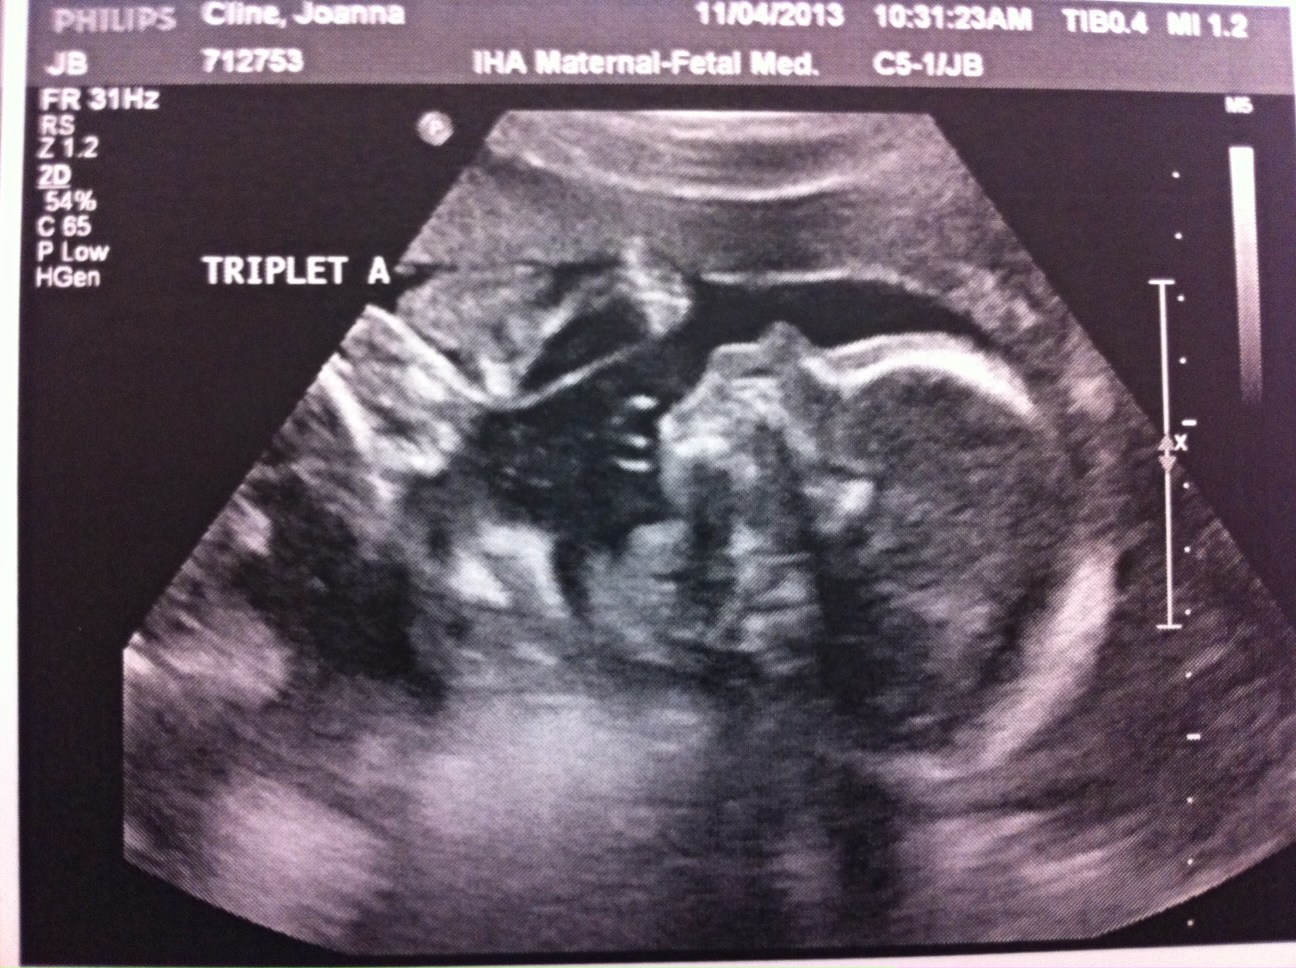

Obviously 24 weeks is still very early (and risky) and we don’t want these babies born yet but it’s still a great checkpoint in my pregnancy. Fortunately, everything looked fantastic at my appointment today. A, B and C looked great and my body is currently a fortress sealing them in where they belong.

Two photos are attached. This week, only A wanted to show his face. And I attached a V Day photo of me. I’m really not sure how my belly is going to get bigger but I’m told it will happen!